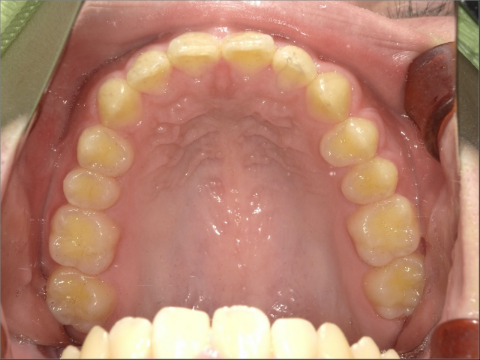

BEFORE

AFTER

ご年齢 15歳女性 治療期間 2022/07/02〜2023/12/02(1年5ヶ月)

診断 110,000円(税込) アライナー 660,000円(税込) リテーナー 55,000円(税込)

ご年齢 15歳女性

治療期間 2022/07/02〜2023/12/02(1年5ヶ月)

診断 110,000円(税込)

アライナー 660,000円(税込)

リテーナー 55,000円(税込)